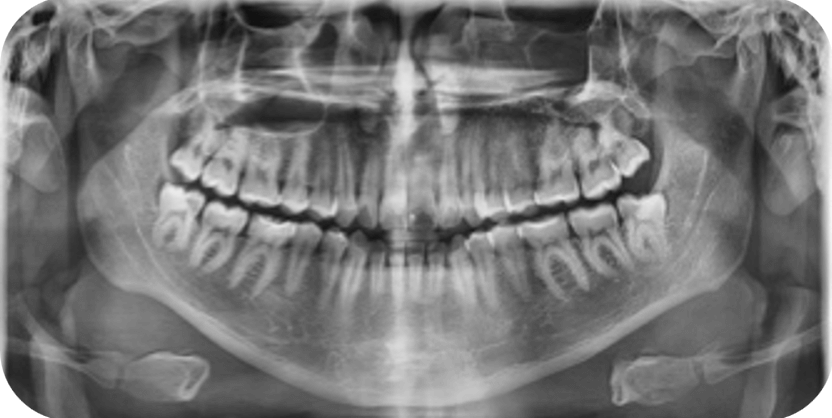

En la radiografía panorámica se observa simetria de las ramas mandibulares, presencia de 32 OD erupcionados, obstruccion parcial de la fosa nasal izquierda y seno maxilar izquierdo reducido.

Fig 4.2 Radiografia panoramica inicial